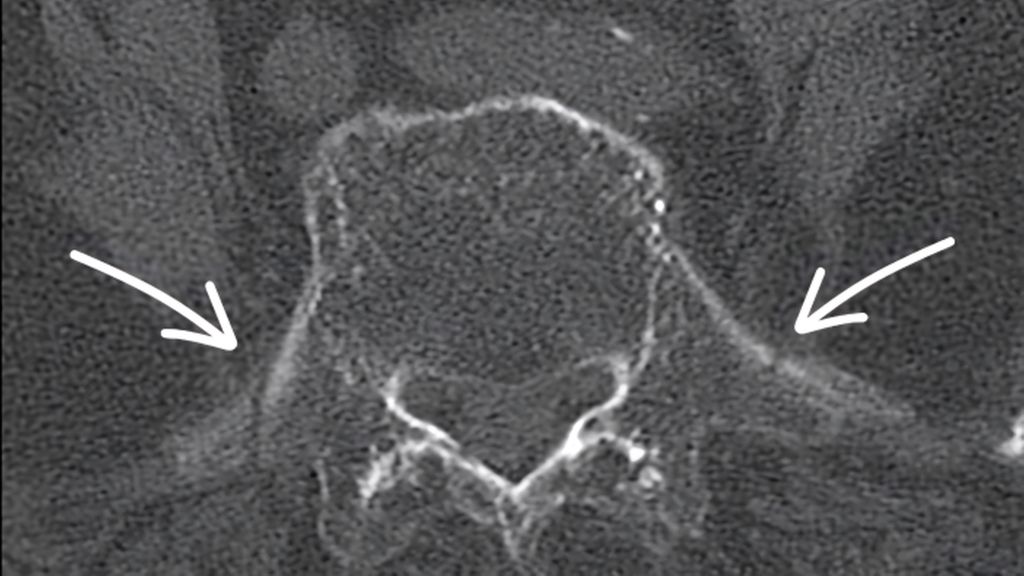

Die Diagnostik von Fragilitätsfrakturen des Beckens kann mit Schwierigkeiten verbunden sein. Fragilitätsfrakturen zeigen sich durch die intakten Bandstrukturen oft nicht oder nur wenig disloziert.8–10 In der konventionellen Röntgendiagnostik wird das Ausmaß der Verletzung, insbesondere des hinteren Beckenrings, oftmals unterschätzt. CT und insbesondere das Dual-Energy-CT (DECT) erreichen eine deutlich höhere Sensitivität und Spezifität für Pathologien des hinteren Beckenrings (Abb. 1).11 Die standardmäßige Durchführung eines MRT hat sich bislang nicht durchgesetzt, kann im Einzelfall jedoch bei klinischem Frakturverdacht und unauffälligem CT ergänzt werden.12

Abb. 1:a) 81-jährige Patientin mit rechtsseitigen Oberschenkelschmerzen nach Stolpersturz vor 3 Wochen, alleine lebend, mit Gehstock mobil. Erneute Vorstellungen mit Infiltration des Kniegelenkes und des rechtsseitigen Iliosakralgelenkes. Stationäre Aufnahme bei Verschlechterung des Allgemeinzustandes und immobilisierenden Schmerzen nach insgesamt 36 Tagen. b–d) Die CT-Bilder zeigen eine bilaterale Sakrumlängsfraktur mit Querfraktur auf Höhe S1/2 sowie Frakturen beider Querfortsätze von LWK 5

Am hinteren Beckenring muss insbesondere der speziellen Anatomie des Sakrums mit häufig vorliegenden Übergangsanomalien Beachtung geschenkt werden. Typische Zeichen wie schräg abfallende Ala, persistierende Bandscheiben in S1 oder das „tongue in groove sign“ deuten auf eine Anomalie des Sakrums hin, die eine sichere Schraubenplatzierung in den S1-Korridor deutlich erschweren oder gar unmöglich machen kann. Eine suffiziente präoperative Planung ist in jedem Fall nötig, um Schraubenfehllagen oder iatrogene Nervenschäden zu vermeiden.16

Abb. 7a: S1-Korridor für transsakrale Versorgung ungeeignet, Alternativen in S2 oder schräg verlaufende SI-Schrauben möglich, präoperative Planung!